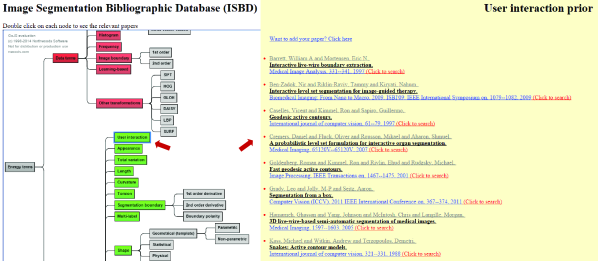

In this section, we review the prior knowledge information devised to improve image segmentation. Table 1 presents some of these important priors and compares them in terms of the nature of achievable solution due to a given formulation (i.e. globally vs. locally optimal), metrication error, domain of action (continuous vs. discrete), and other properties. We also created an interactive online database to categorize existing works based on the type of prior knowledge they use. We made our website interactive so that researchers can contribute to keep the database up to date. Figure 8 illustrates a snapshot of our online database showing different prior information that have been used in the literature for targeted image segmentation.